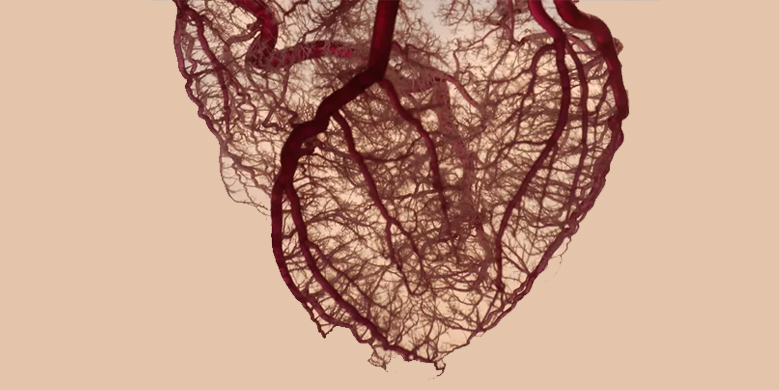

A "tight" (say 80-85%) blockage in the heart arteries may still supply adequate blood to the heart in resting stage, thus leading to a "Normal" ECG. It is only when the heart is exercised, the heart rate increases, and the "tight" block prevents any increase in the blood flow, that the patient will experience chest pain/ or the ECG becomes abnormal.

A. Unfortunately, this test is not very accurate. Some cases with "tight" blockages may show no changes on TMT (False negative), whereas some cases with no blockages may also show significant ECG changes (False Positive). Hence, Clinical judgement is paramount. Nevertheless, TMT continues to be used widely as a screening test to rule out blockages in heart arteries.